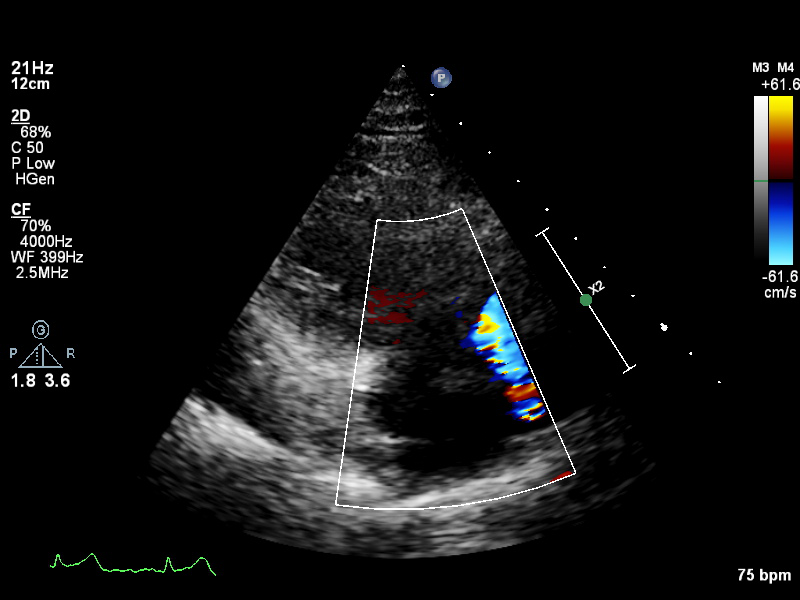

a4ch-ra a4ch-ra Apical 4-chamber focused on the right atrium, or colour Doppler on TV/RA

plax-full-rv-ao plax-full-rv-ao Focus on RV & aorta or colour Doppler over RV/AV/Aorta

plax-tv plax-tv Parasternal inflow view including tricuspid valve

plax-valves-av plax-valves-av PLAX focused on the aortic valve

plax-valves-mv plax-valves-mv PLAX focused on the mitral valve